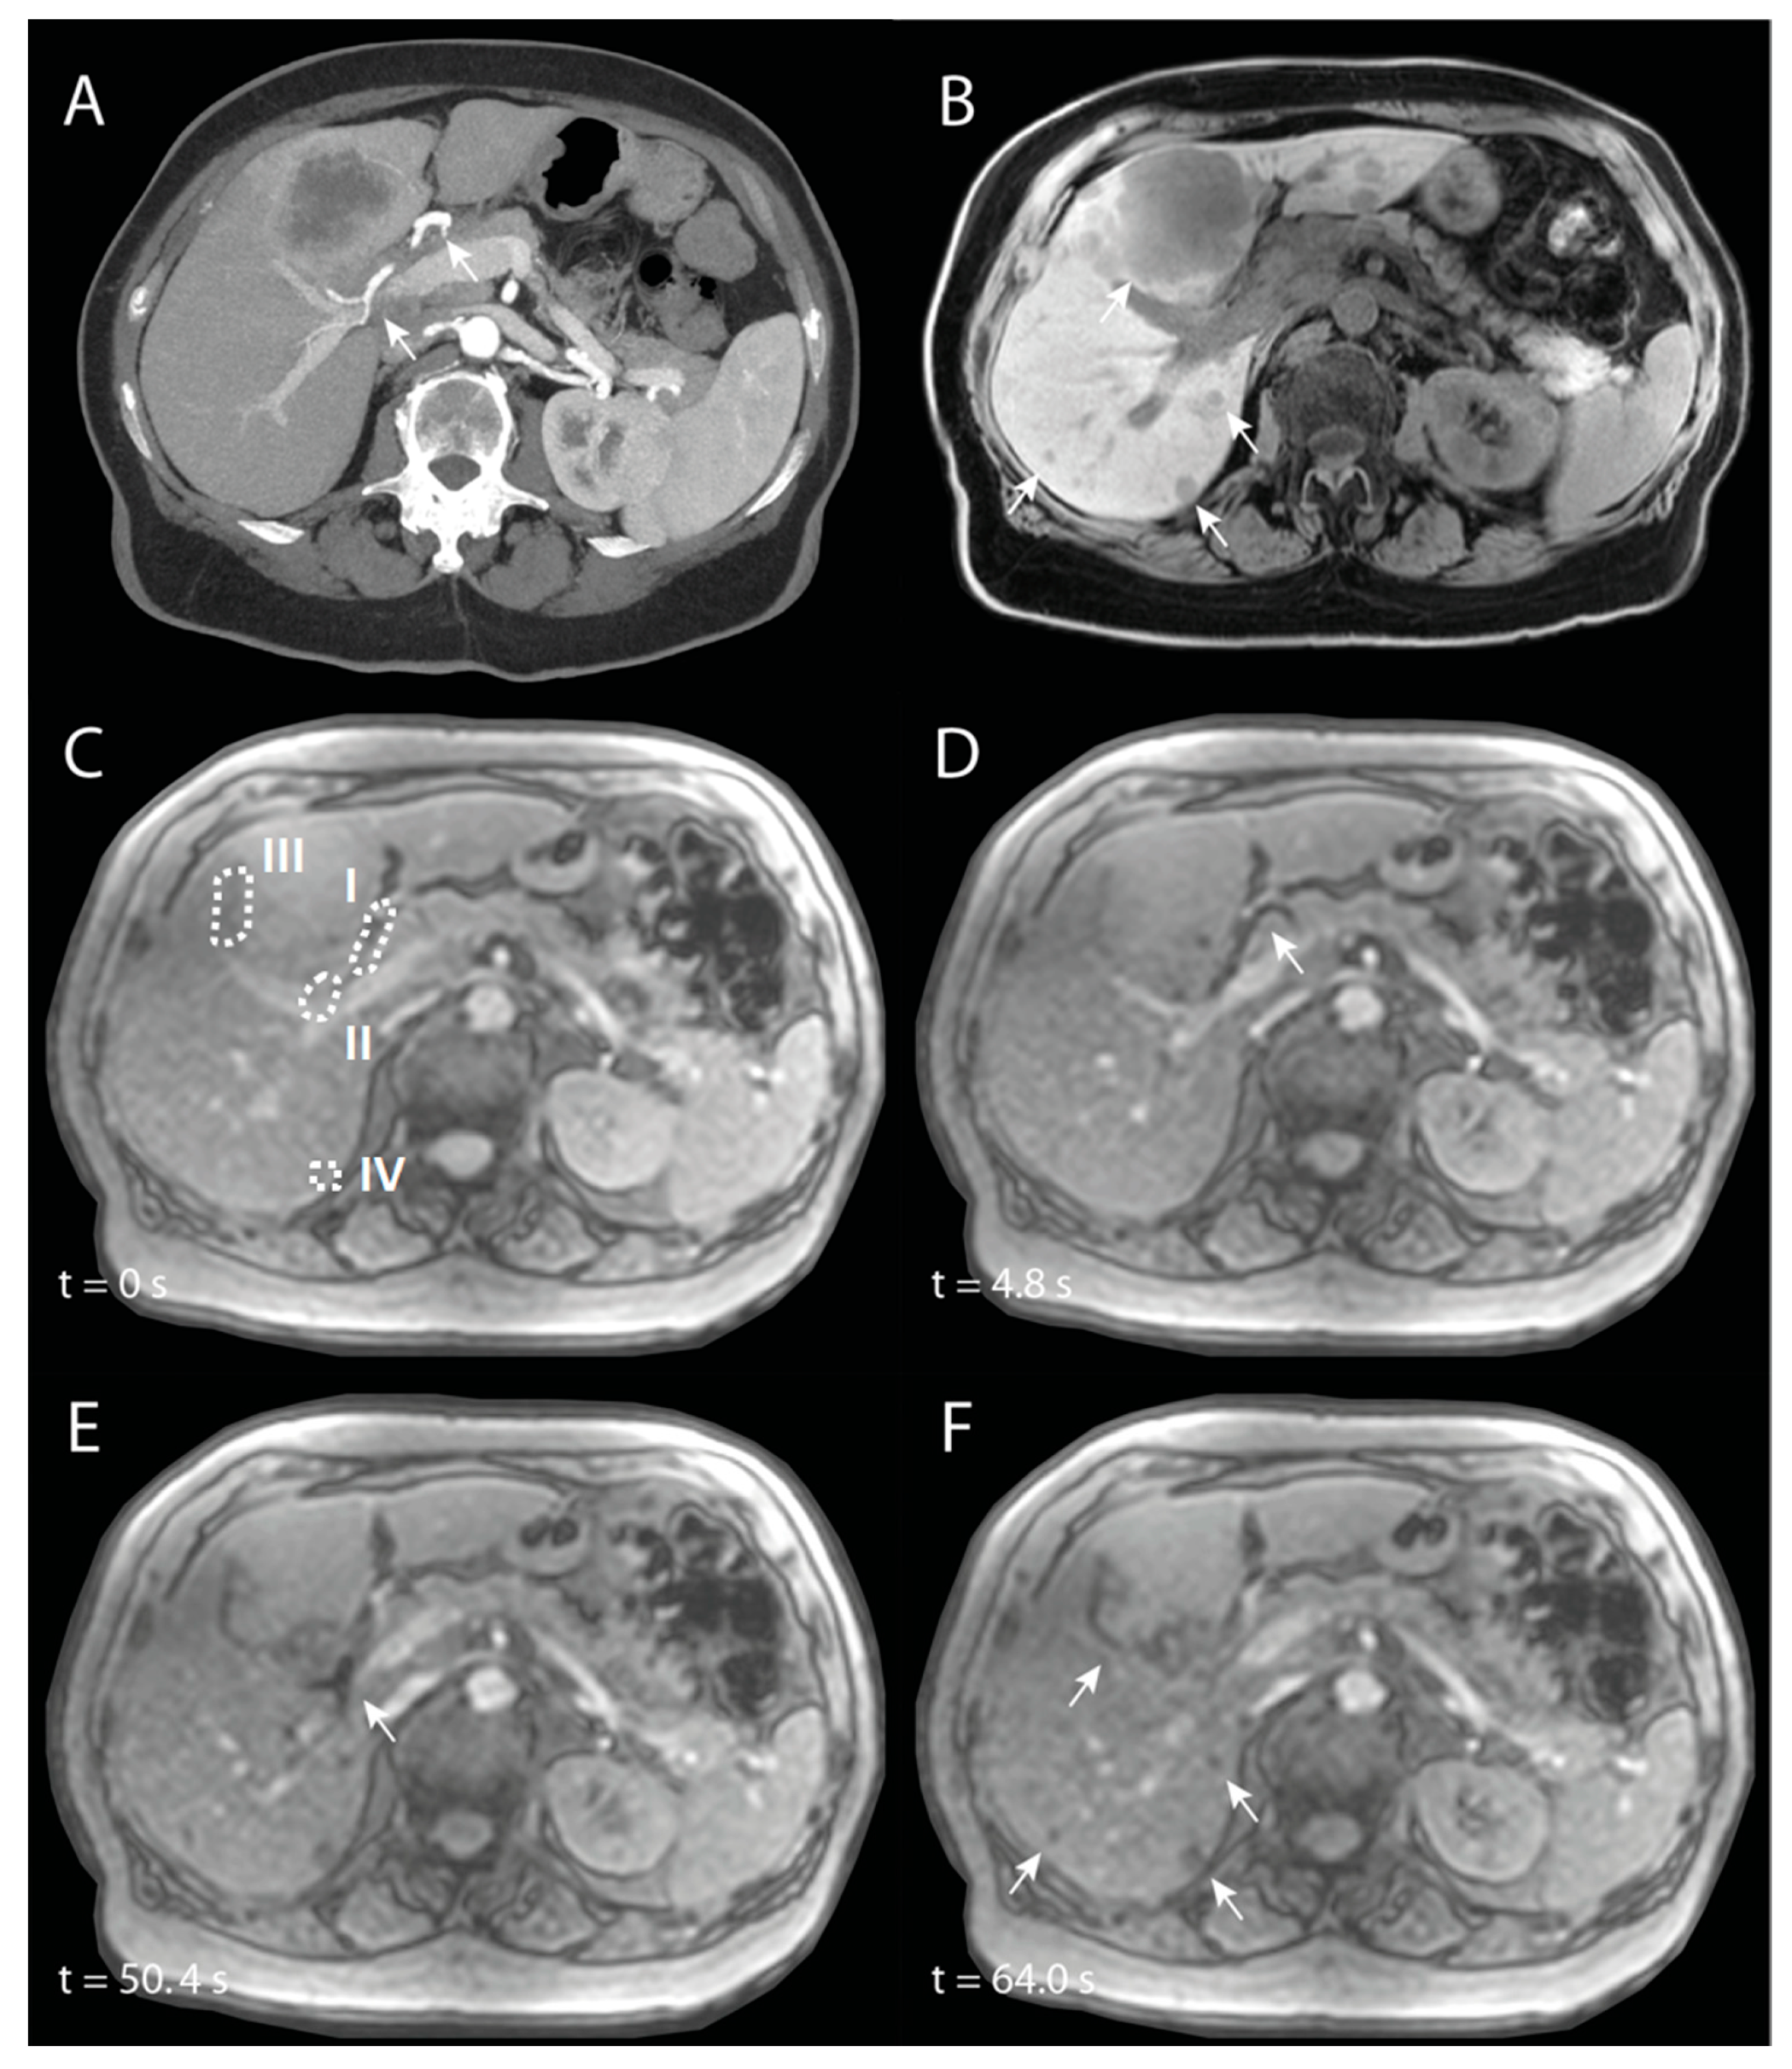

SIRT was performed in a 74-year-old patient with intrahepatic cholangiocarcinoma. The main lesion was located in Couinaud segments 4A and 4B, and there were multiple satellite lesions in all other liver segments (see Figure 9A,B). A whole-liver SIRT was performed under near real-time MR-imaging, starting with the right hemiliver. The microcatheter was positioned proximal in the right hepatic artery (RHA). In Figure 8, angiography of the entire liver and selective angiography of the RHA are visualized. In Figure 9C–F, different chronological frames of the near real-time imaging during the injection of 30% of the total dose of holmium microspheres are presented. A video of this near real-time imaging series is available online (Supplementary Video S1).

Figure 9.

Imaging of a patient with intrahepatic cholangiocarcinoma, of whom the right hemiliver is treated with selective internal radiation therapy. (A) is a maximum-intensity projection of an arterial phase CT in which the right hepatic artery (RHA) is annotated with arrowheads. (B) is a corresponding non-enhanced T1-weighted MRI in which multiple tumours are visible (arrowheads). (C) to (F) are chronologic frames from the near real-time imaged holmium-166 microspheres injection: (C) is just before injection, with VOIs used for signal quantification annotated with dashed lines. In (D), there is loss of signal because of the microspheres in the proximal RHA (arrowhead) and in (E) in the more distal RHA (arrowhead). (F) is the end of near real-time administration, in which there is loss of signal mainly at the tumour sites (arrowheads) that was not visible prior to injection (C).

The aforementioned holmium microspheres were administered in multiple smaller injections (total amount = 126 mg), with catheter flushing with NaCl 0.9% in between, as per usual when using the Customer Kit for microsphere injection. During the first half of the near real-time imaging, a loss of signal is seen in the proximal RHA (Figure 9D). In the second half, this loss of signal was mainly seen more distally in the RHA (Figure 9E), probably as a result of a small breathing motion of the patient, because of which the proximal RHA moved out of plane and the distal RHA entered the imaging plane. Almost immediately after start of injection, loss of signal is seen accumulating in the tumours (Figure 9F).

Quantification of the signal intensities in four different VOIs (proximal RHA (I), distal RHA (II), the edge of the large tumour (III), and the small tumour (IV)) are visualized in Figure 10. The transient loss of signal during the initial injections of the microspheres were clearly visible in the proximal RHA, with the last drop in intensity around 30–40 s, after which the loss of signal occurred more distally in the RHA. In both tumours, there was a rapid decrease in signal intensity during the first injection of microspheres, after which the intensity kept decreasing during the remainder of the injections.